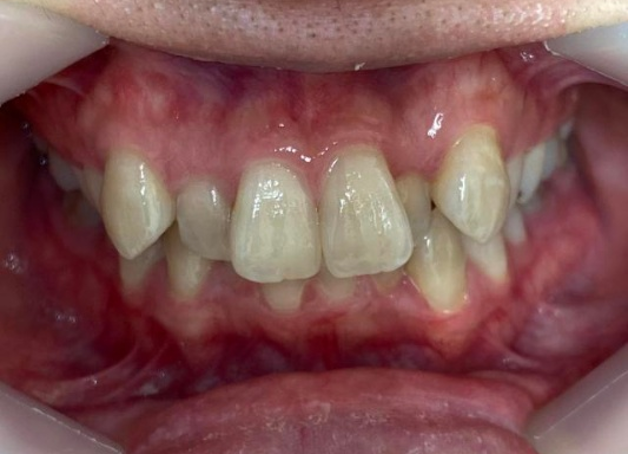

拝見したところ、上下とも歯が並ぶためのスペースが不足しており、全体的に歯が重なり合って生えている重度の「叢生(そうせい)」でした。

見た目が気になるだけでなく、虫歯や歯周病のリスクも高くなっていました。